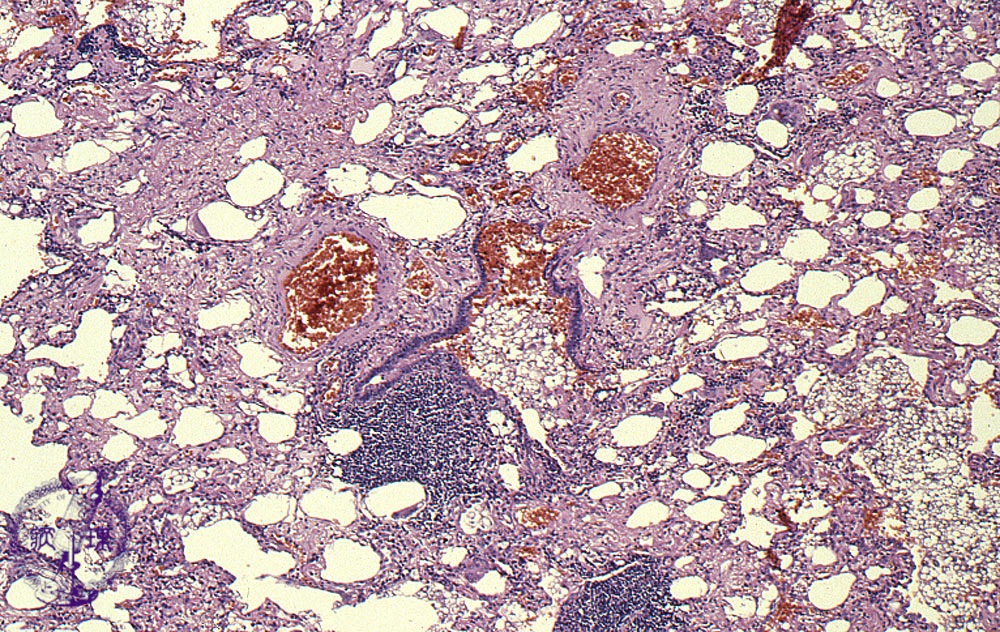

Microscopic view (HE stain, low power view): Aspirated lipoid material fills the alveoli accounting for the yellow color seen grossly and the name ggolden pneumonia.h